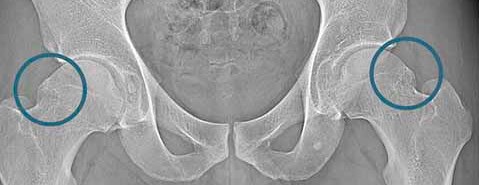

There are many causes of hip joint pain, one of which is femoroacetabular impingement (FAI). This condition was first described in 2003 as a repetitive abnormal contact between the acetabulum and the femoral head, which can lead to degenerative changes and damage to the articular cartilage and labrum.

FAI is caused by abnormal bone growth, which may occur in the femoral head, acetabulum, or both.

Cam Impingement: This occurs when a bony deformity develops at the junction of the femoral head and neck. This protrusion may hinder full rotation of the femoral head within the acetabulum or rub against the labrum and cartilage, causing damage. Statistics indicate that Cam impingement most commonly affects young men and is less frequent in women.

Pincer Impingement: This occurs when a bony deformity forms on the edge of the acetabulum. The resulting overhang deepens the socket in some areas, limiting the femoral head's rotation or damaging the labrum. Pincer impingement is most common in middle-aged women.

Imaging plays a vital role in diagnosing FAI. X-rays can confirm the condition by revealing bony deformities on the femur and/or acetabulum. Magnetic resonance imaging (MRI) with contrast (arthrography) may also be used to detect labral damage.